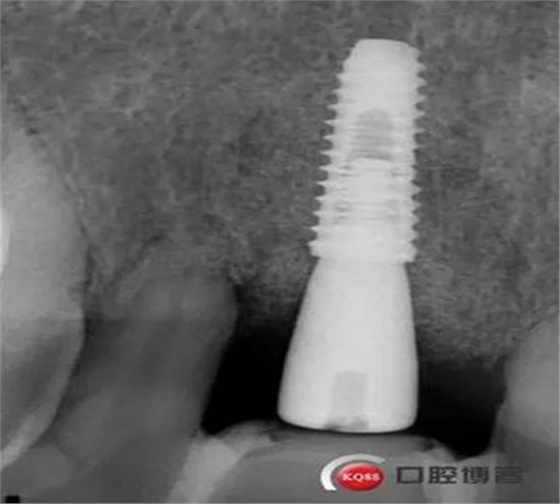

患者:王XX 年齡:42 上前牙松動數(shù)年,從未做過任何處理,今來院就診;檢查:CBCT示上前牙區(qū)顎側(cè)一大小約7x7mm囊腫;治療計劃:即刻種植同期摘除囊腫

術后CBCT